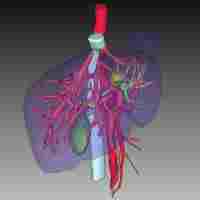

| Abstract | With microtrauma becoming a consensus, in order to improve surgical treatment capability, the clinical application of laparoscopic multiorgan resection is becoming more and more complicated and diversified. Recently, we successfully presented a case of transvaginal specimen extraction surgery that included laparoscopic anatomical left hemihepatectomy combined with laparoscopic total hysterectomy and bilateral adnexectomy and the pelvic and para-aortic lymphadenectomy. The patient, a 75-year-old woman, was hospitalized with abnormal vaginal discharge and bleeding. The pathologic diagnosis of uterine curettage was endometrioid adenocarcinoma. After completing examinations such as color Doppler ultrasound, CEUS, MRCP and thoracoabdominal enhanced spiral CT, preoperative diagnosis was considered as endometrial cancer and a space-occupying lesion in the liver (primary or secondary site?). No lymphatic or distant metastasis had been found. We also excluded Lynch syndrome by digestive endoscopy and gene sequencing. After a multidisciplinary consultation, the patient underwent surgery under general anesthesia on 24 September 2021. The operation was completed uneventfully in 6 hours, then the patient was transferred to the ICU for follow-up monitoring. The patient began to eat and was able to leave bed on the 4th postoperative day. According to immunohistochemistry, the patient's postoperative diagnosis was intrahepatic cholangiocarcinoma (ICC) and endometrial cancer. Compared with open surgery, laparoscopic multiorgan resection with natural orifice specimen extraction surgery (NOSES) has many advantages such as fewer traumas, shorter recovery time, and better postoperative quality of life. However, combined large-scale laparoscopic surgeries of different organs can be challenging for surgeons and anesthesiologists. No similar cases have been searched. |